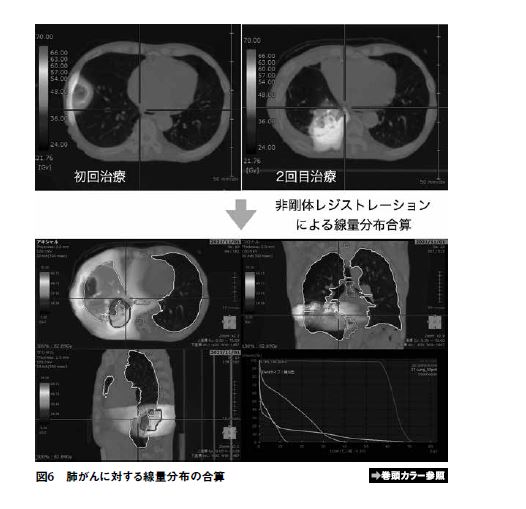

線量分布の合算

放射線治療中に腫瘍の縮小や体位の変更などがあり治療計画CT撮影時と違いが出てきた場合には再度治療計画CTを撮影しリプランすることや、過去に照射歴があった患者に対し治療計画を作成する機会はしばしばある。その際にこれまでに照射した分の線量を新しく撮影した治療計画CTに反映させることは、体位や輪郭が変化しているため容易ではなく、その線量を考慮した上でリプランできる治療計画装置は少ない。SYNAPSE radiotherapyでは新しい治療計画CTと過去の治療計画CT間で非剛体レジストレーションを行うことで過去に照射された線量分布を新しい治療計画CT上にのせることが可能であり、過去の線量を考慮した上での治療計画の大きな手助けとなる(図6)。またリプランで作成した治療計画に過去の治療の線量を反映させることで、線量分布を合算した上での標的やリスク臓器の線量を見ることが可能である。